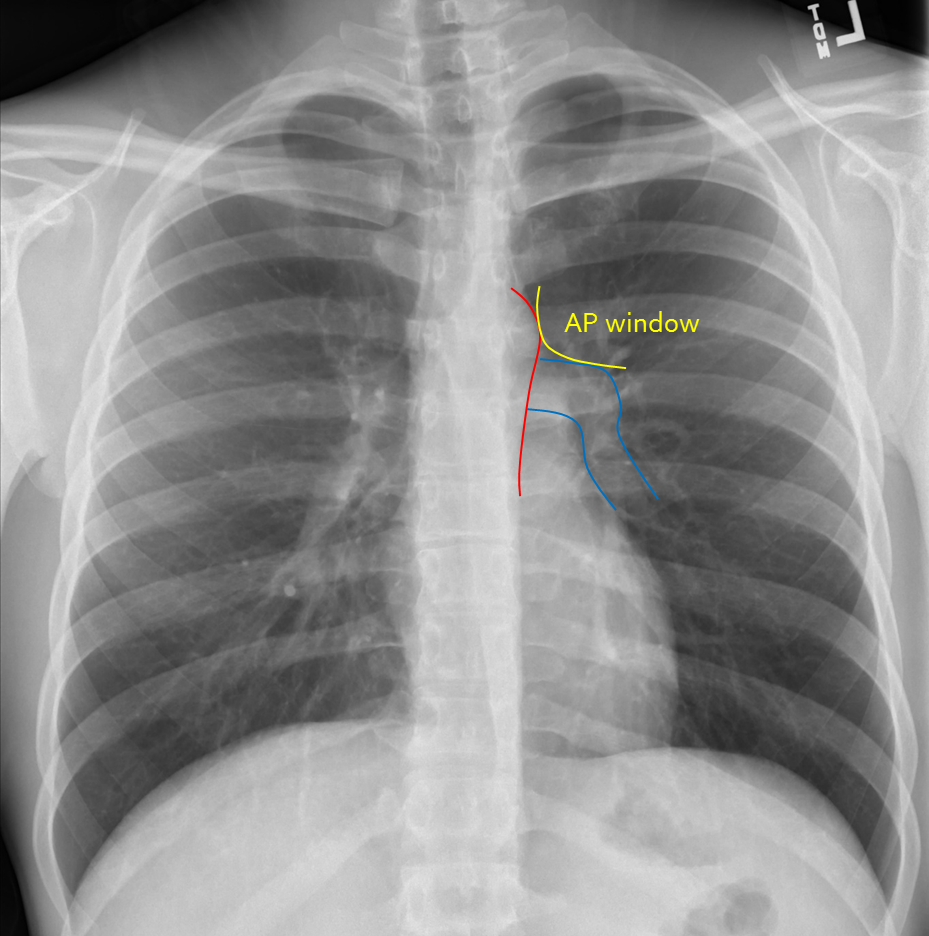

Xray chest PA (posteroanterior) view showing the "4bump" left heart What Is Chest X Ray Spot The interpretation of a chest film. A spot on the lungs usually refers to a pulmonary nodule. This is a small, round growth on the lungs that shows up as a white spot on image scans. In fact every radiologst should be an expert in chest film reading. They are windows into the health of your thoracic cavity, including lungs,. What Is Chest X Ray Spot.